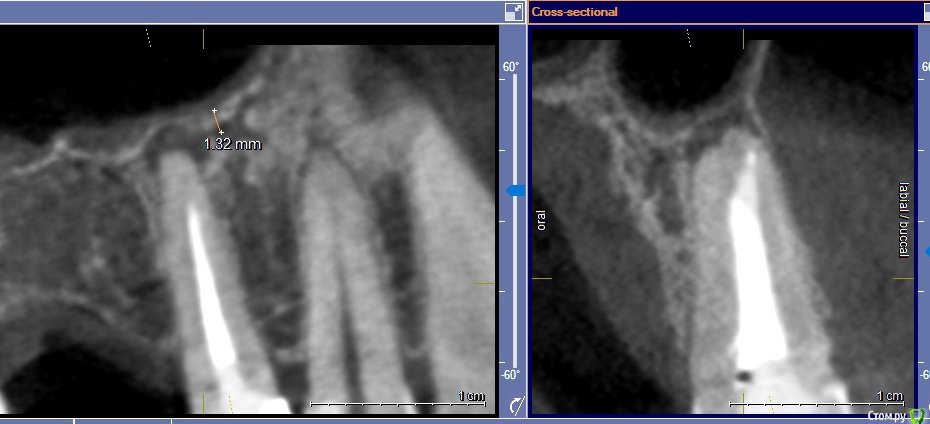

Посмотрите пожалуйста КТ 5го зуба. Гранулёма на корне обнаружена лет 5 назад. Зуб делался лет 17 назад.

(Канал, похоже, чуть в сторону пройден, апикальное отверстие чуть левее поэтому, наверное, и выросла киста...)

Гранулёма не росла, не беспокоила. Но вот начала иногда побаливать при накусывании. При простудах чувствуется  дискомфорт.

Имеет ли смысл перелечивать канал? Или лучше резекция? Делают ли резекцию при такой близости к пазухе? (напугали, что никто не возьмется - тк риск перфорации).

Фото в 2х проекциях прилагаю. Заранее благодарю!